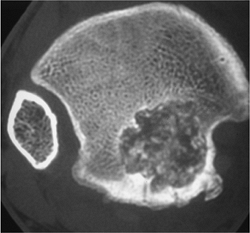

FIGURE 10-8 Intracapsular osteoid osteoma. Coronal T1-weighted (A) and fluid-sensitive (B) weighted images showing a large area of signal abnormality in the right femoral neck. (C) Axial T2-weighted image shows fluid in the joint with a small high signal intensity nidus (arrowhead) and surrounding edema. (D) Axial CT image demonstrates the lucent nidus (arrowhead) more clearly.